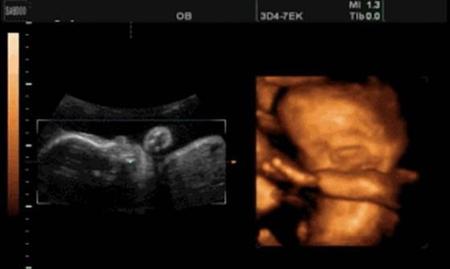

男翻女和女翻男只有一种情况,那就是B超没有看清楚。

可能和打B超的人技术有关。也可能和孩子的体位有关。更有可能是孩子器官外形模糊,没有看清楚。

总之,只能是人为失误,不可能是真的翻转了!

至于现实生活中,很多人会出现女翻男,或男翻女的说法,讲的通俗一点就是本来通过某种手段得知,宝宝是个男宝,结果生下来的时候却发现是个女宝。这个情况是存在的,但是不由于宝宝性别改变造成的,而是生前的那种了解胎儿性别的手段错了,即使是B超也存在看走眼的时候。